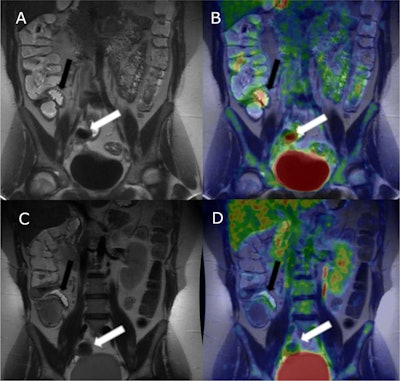

A 27-year-old female with small bowel Crohn’s disease-related inflammation in terminal ileum (black arrows pointing at a distal skip lesion and white arrows pointing at a proximal skip lesion). In the first diagnostic T2-weighted MRE, inflammation is barely seen, sMARIA score (simplified Magnetic Resonance Index of Activity) 1 (A). In fused F-18 FDG-PET/MRE (B), inflammation is clearly seen in both segments, SUVMax 6.6. Follow-up F-18 FDG-PET/MRE was done 98 days after the diagnostic. No visible inflammation in T2-weighted MRE, sMARIA score 0 (C), and a clear decrease in inflammation is seen as F-18 FDG-activity has subsided in fused F-18 FDG-PET/MRE, SUVMax 1.3 (D)European Journal of Nuclear Medicine and Molecular Imaging“To our knowledge, this is the first study to demonstrate that F-18 FDG-PET/MRE may be used in the follow-up of small bowel [Crohn’s disease] to monitor response to medical treatment,” the group wrote.